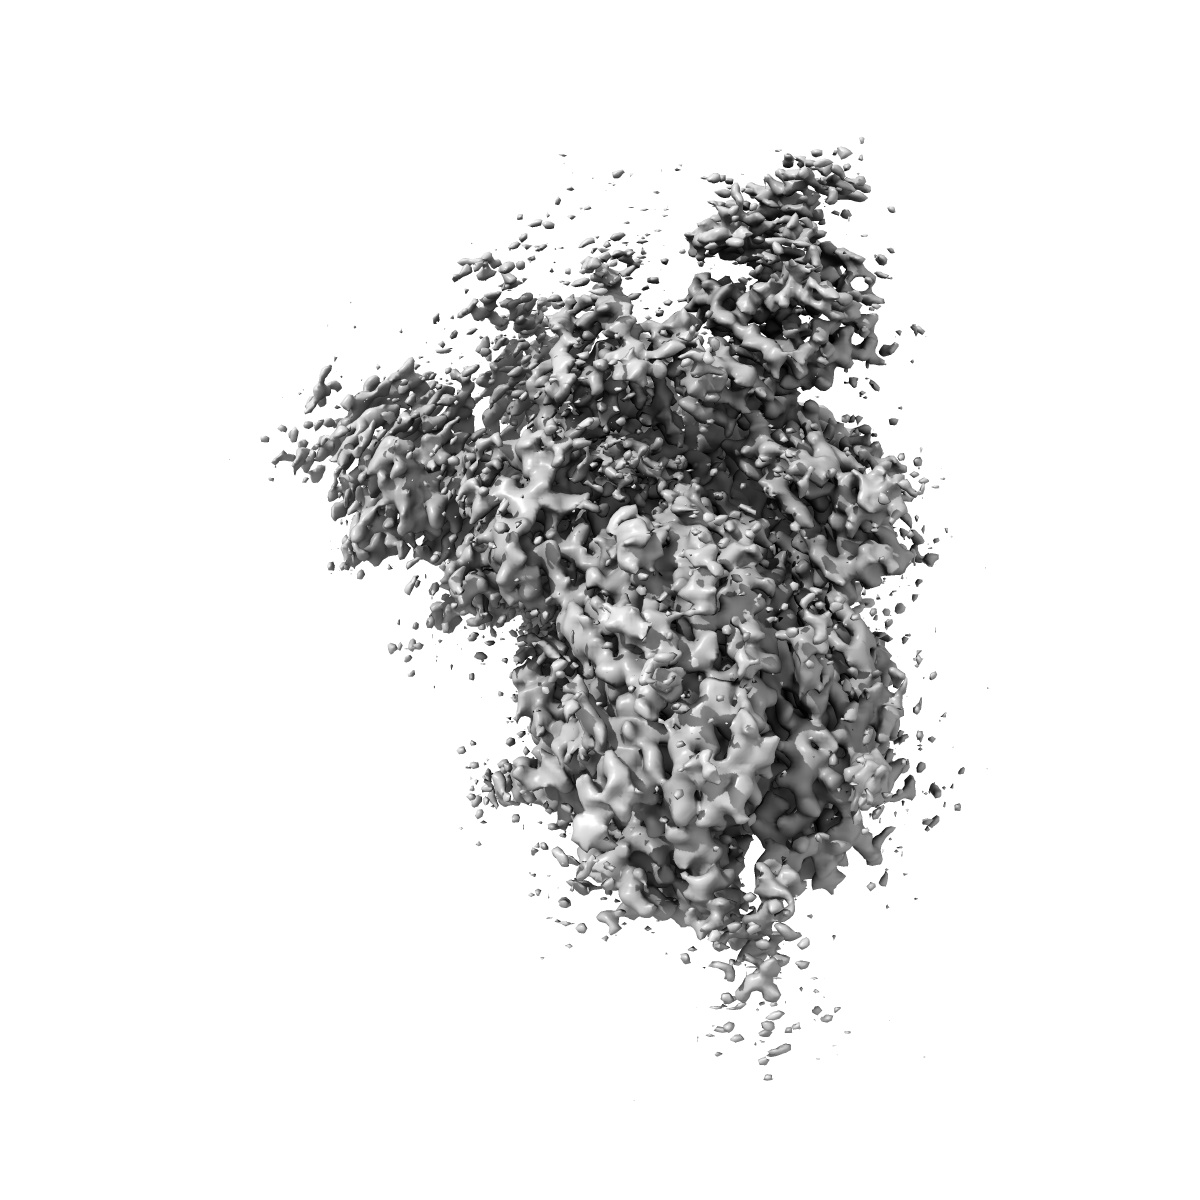

Structure of Covid Spike variant deltaN25 with one erect RBD

Single-particle3.52 Å

Sample: Covid Spike variant deltaN25